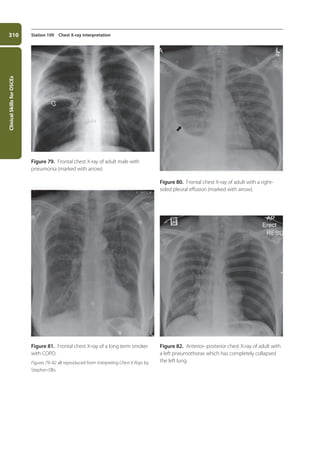

109. Chest X-ray interpretation 306